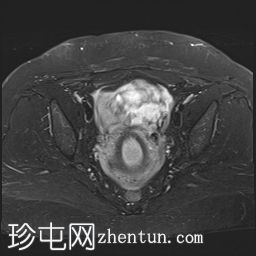

冠状位

T1加权像

可见子宫外腹腔内妊娠囊,内含胎儿组织。

该妊娠囊向后推移子宫,并与剖宫产瘢痕凹陷处紧密相连。

该妊娠囊与相关肠袢无法分离。可见其与性腺血管密不可分,且性腺血管明显突出。

胎盘位于妊娠囊后方,紧贴子宫前壁。

沿妊娠囊下缘可见一处异质性局灶性积液,最大轴向尺寸约为 8.4 × 5.5 cm,T1 加权像呈异质性高信号,T2 加权像呈异质性中等信号,T1 脂肪抑制序列未见信号下降,提示为血液成分。该积液压迫膀胱。

可见周围脂肪间隙呈条索状改变。

左侧卵巢无法辨认。

右侧卵巢未见实性或囊性肿块。

子宫体积增大,后倾,子宫内膜厚度约 1 cm,子宫下段前壁可见局灶性变薄(既往子宫瘢痕)。子宫连接区完整,未见肌层肿块。可见子宫内膜腔边缘有血性分泌物。